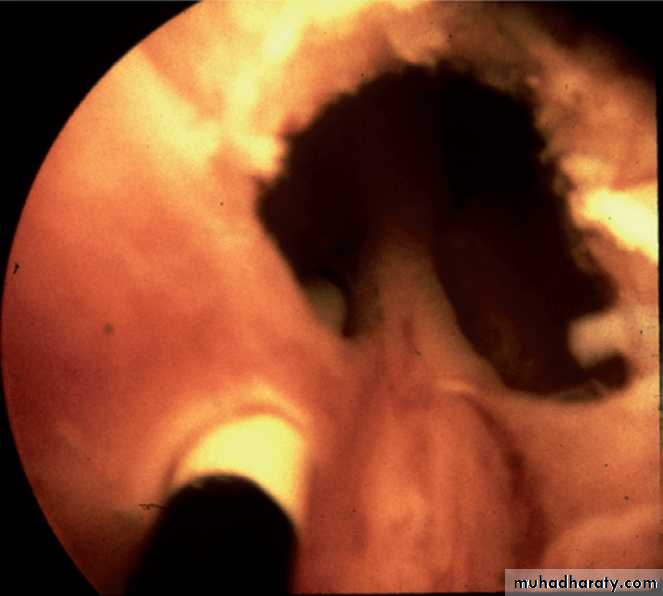

Cystoscope: by visulization of the valve

PUV (cystoscope)